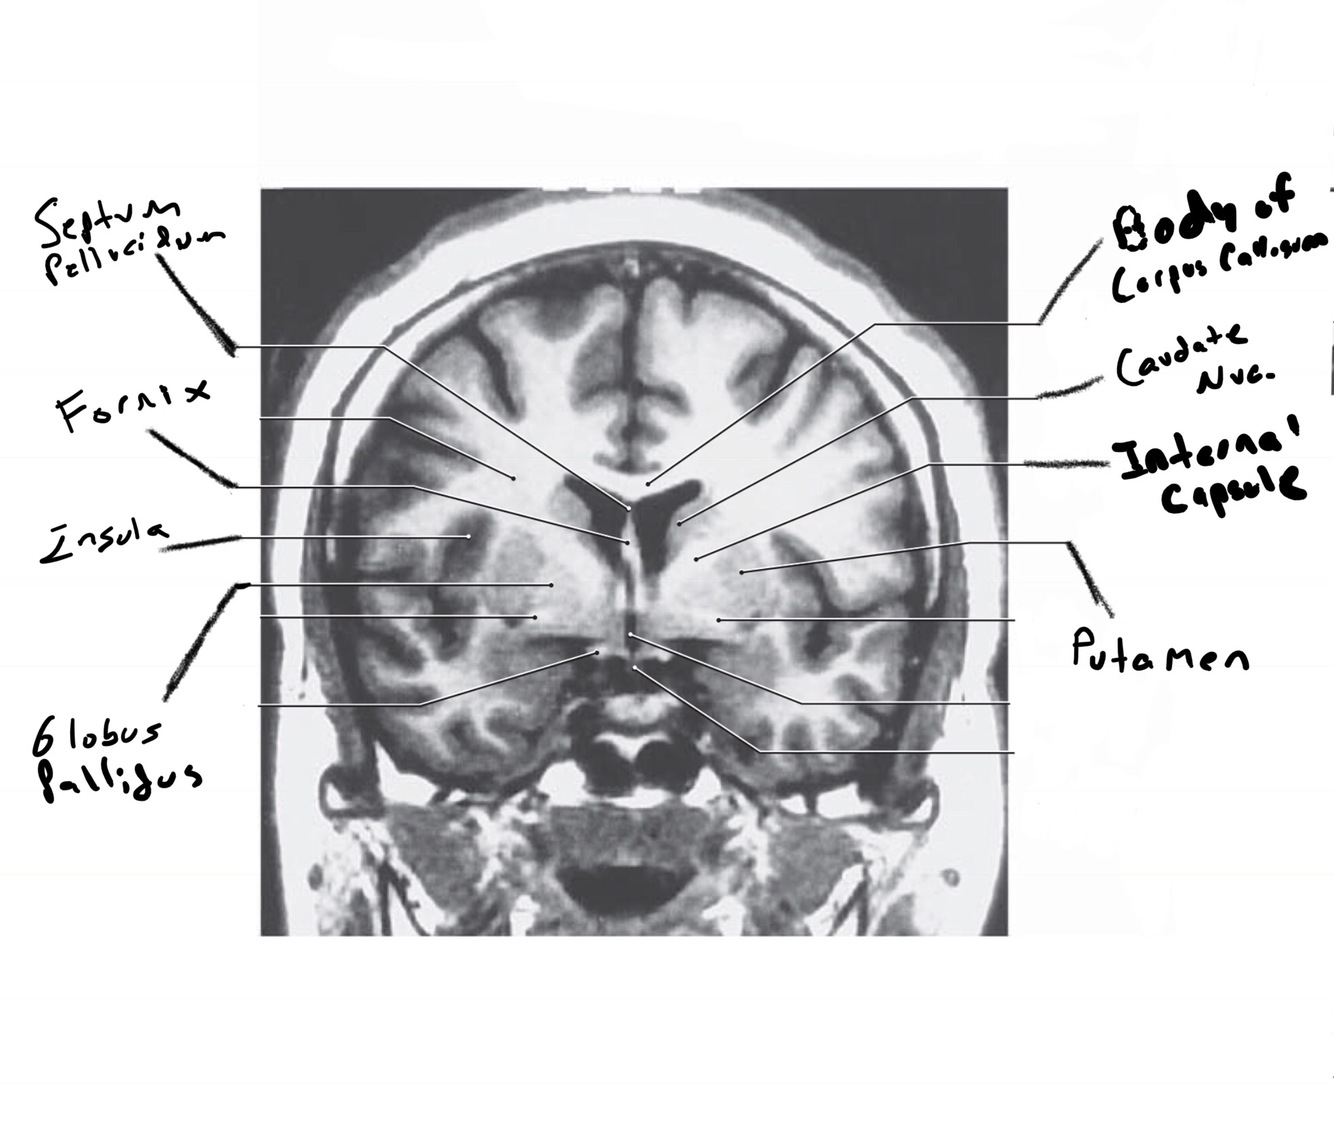

The structure indicated by the red line is?

The structure indicated by the red line is? BONUS: SYMPTOMS IF THERE IS A LESION